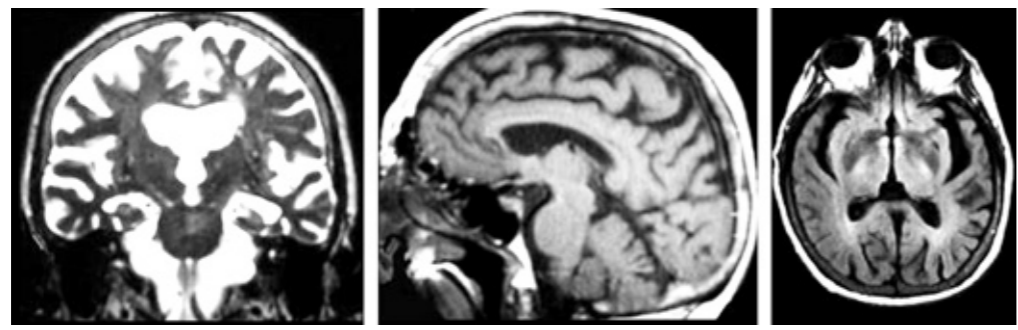

Asimismo, los pacientes que presentan enfermedad de Alzheimer muestran una atrofia cerebral que comienza en los hipocampos y amígdalas. Después, en lóbulos frontales y temporales. Con el avance de la enfermedad, todo el cerebro queda perjudicado. Así, tales daños concuerdan con el avance de la sintomatología de dicha afección.